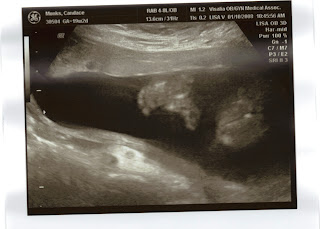

Here are the first pictures of our little girl Chloë Addison Tredway. The first picture is her left-side profile and the second picture is her right-side profile. She appears to be sucking her thumb or fingers. Everything appears to be fine, the doctors tell us that she is a healthy little 10 oz. girl. That is not even the size of a coke can! Chloë's expected due date is June 2nd, 2008! Mommy is doing well, considering the morning sickness that is getting better.

This picture is of her little dancing feet. This one is so cute because you can see her little feet and toes. She is going to be our little dancer for Jesus. Keep posted, we will be putting up some 4D pictures soon.